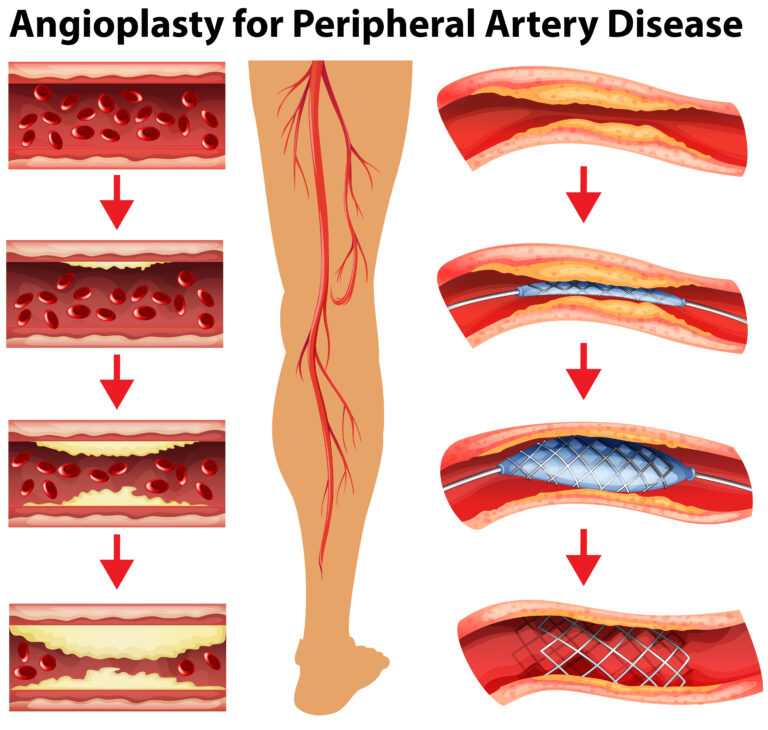

1. Angioplasty (Balloon Procedure)

- A minimally invasive day-care procedure

- A balloon catheter is inserted into the narrowed artery

- The balloon inflates, widening the artery and restoring blood flow

- Provides immediate relief from pain and improves walking ability

Benefits of Angioplasty

• No major cuts or scars

• Quick recovery, often same-day discharge

• Reduces leg pain, improves circulation

• Prevents complications like non-healing ulcers

2. Stenting (Permanent Artery Support)

- Often combined with angioplasty

- A stent (tiny mesh tube) is placed in the artery to keep it open

- Drug-eluting stents prevent re-blockage (restenosis)

Benefits of Stenting

• Provides long-lasting results

• Maintains artery patency (keeps it open)

• Minimally invasive with tiny puncture sites

• Improves mobility and limb health